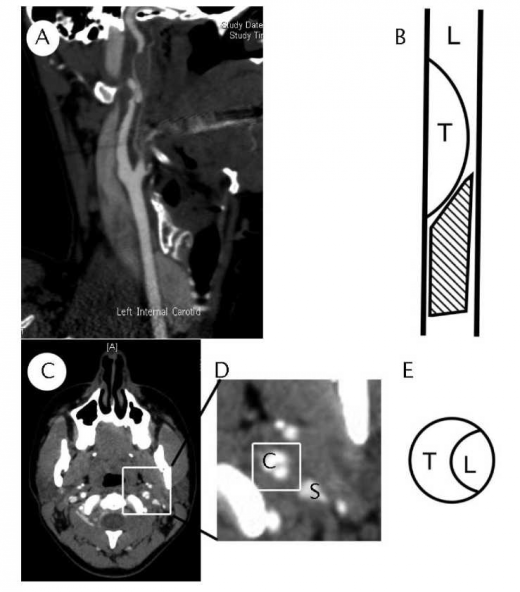

(A) CT angio בשחזור סגיטלי (Sagittal), ניתן להבחין בהיצרות הדרגתית של עורק התרדמה הפנימי, עם מילוי רטרוגרדי.

(B) ציור סכמטי של העורק - L - חלל העורק, T - קריש דם בדופן העורק באתר הדיסקציה, החלק המקווקו מזכיר "מקור ציפור" בחתך.

(C) חתך אקסיאלי (Axial) והגדלה של האזור הרלוונטי ב-(D). ניתן לשם לב לקרבה משמעותית בין עורק התרדמה (מסומן ב-C) לבין זיז הסטילואיד (Styloid process) (מסומן ב-S).

(E) ציור סכמטי של העורק הפגוע בחתך אקסיאלי (L - חלל העורק, T - קריש הדם בדופן).